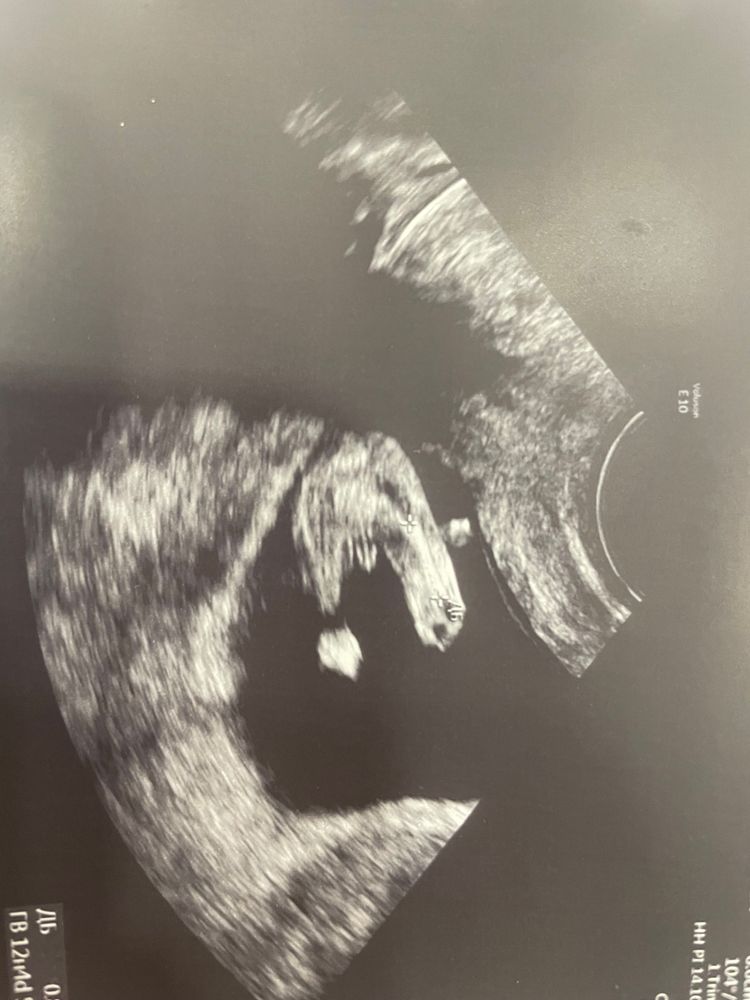

Это половой бугорок, половые органы ещё не сформированы, только под градусом можно определить Изображение

В таком ракурсе не смотрят на данном сроке.Там мерить надо угол наклона.Можете загуглить и почитать.И у М и у Ж сейчас половой бугорок

Не понимаю как все с уверенностью пишут мальчик, если на фото нет отчетливого сформированного органа В 12 недель там почти все одинаково Через месяц все у вас будет хорошо видно)

Надя, это называется половой бугорок, а не уже сформированный орган. В 12 недель только во градусам можно сказать, а органы еще не сформированы

Mari na Lune, в 12 недель ваш врач прикинул градус примерно бугорка и предположил мальчика. Тут же у автора видно только бугорок, но не видно градус бугорка. И как можно определить, что это мальчик, потому что увидели только бугорок?